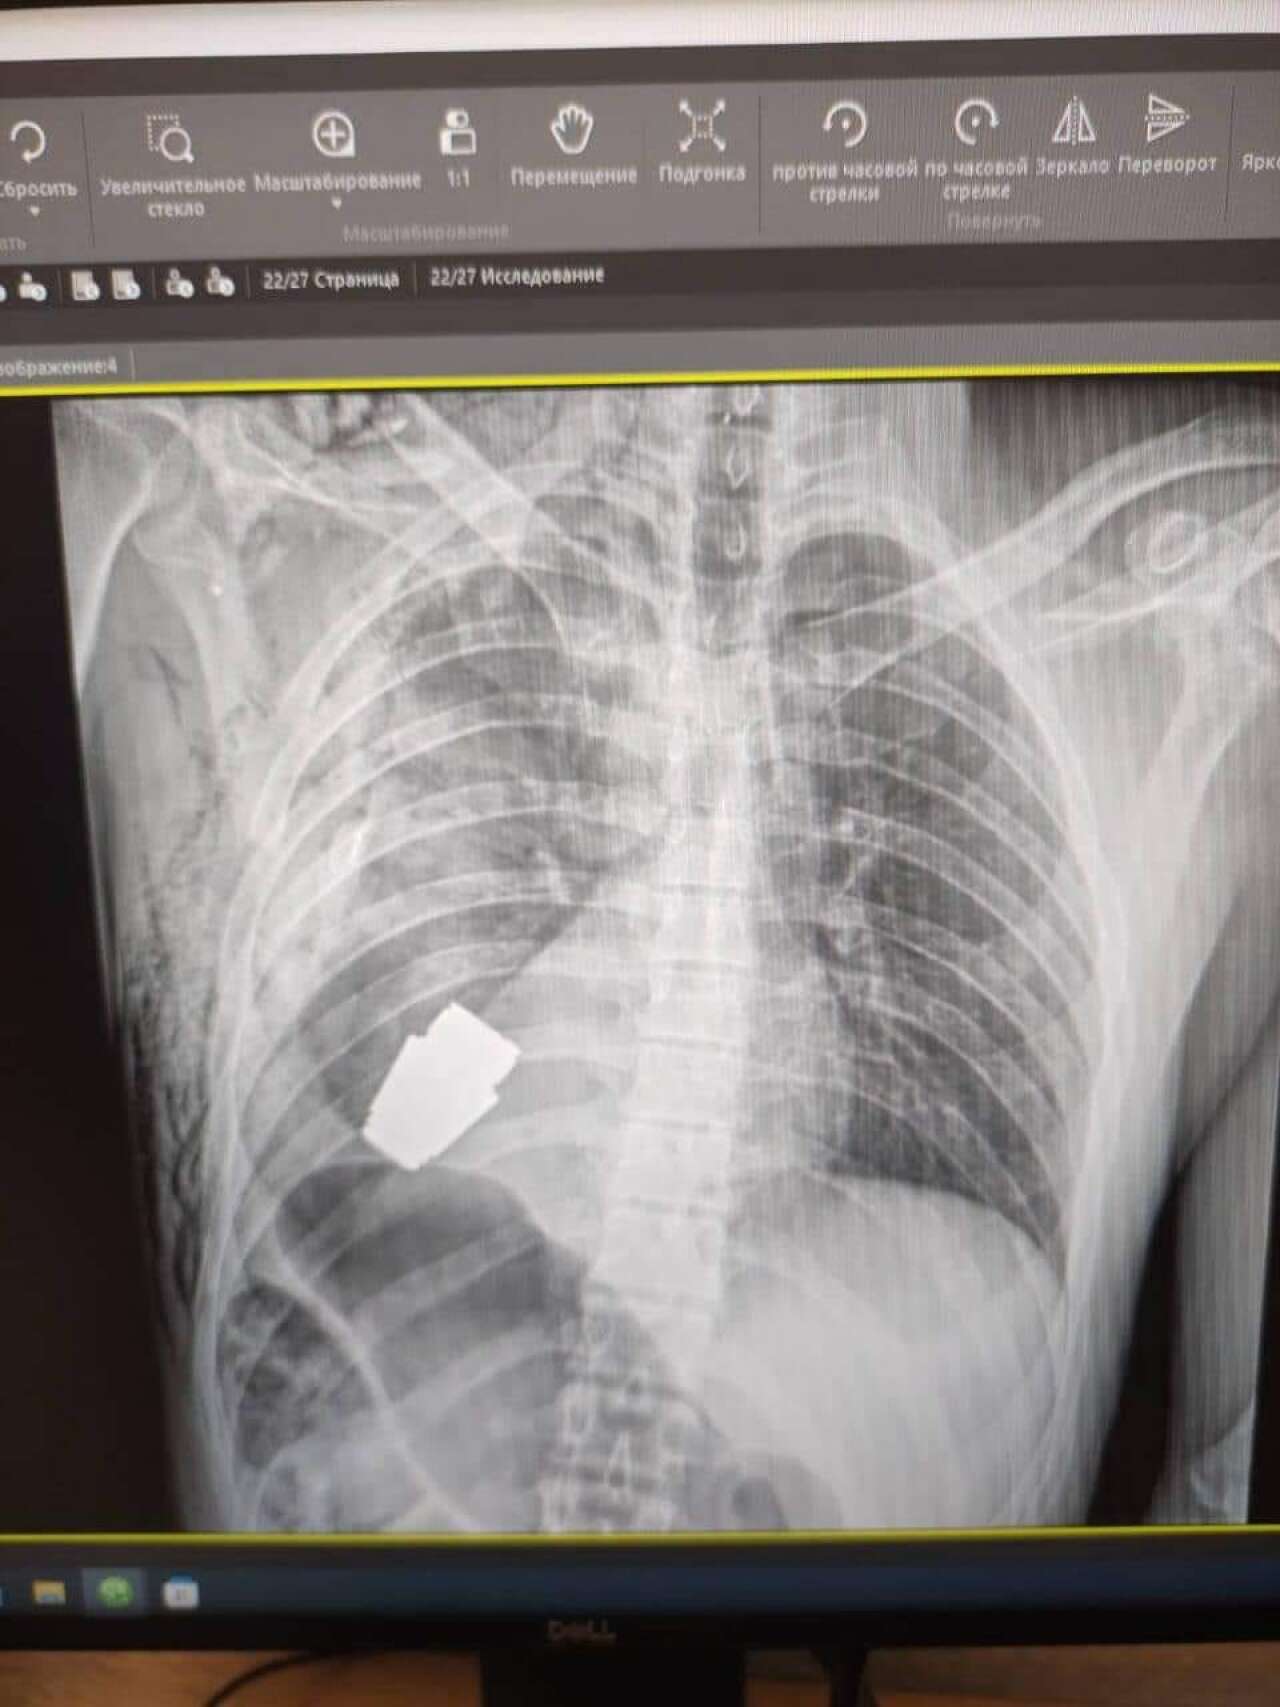

Наші військові лікарі провели операцію з видалення гранати ВОГ, яка не розірвалася, з тіла військовослужбовця.

Операція тривала в присутності двох саперів, які контролювали безпеку медичного персоналу та пацієнта.

Один з найдосвідченіших хірургів ЗСУ, генерал-майор Андрій Верба, працював без електрокоагуляції, оскільки граната могла детонувати у будь-який момент.

Оперативне втручання пройшло успішно, а пораненого військовослужбовця відправили на подальшу реабілітацію та відновлення.